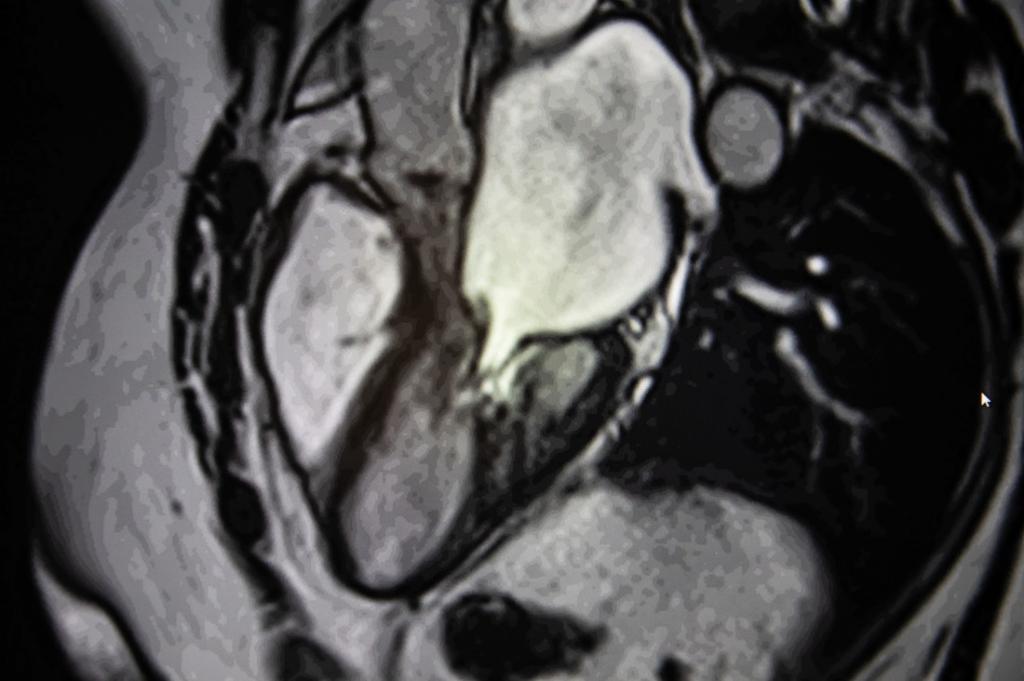

МРТ — этот метод позволяет оценить распространенность патологического процесса.

- ЭХО-КГ. Этот метод позволяет оценить объем камер сердца, фракцию выброса левого желудочка и определить локализацию склерозированных участков.

- Сцинтиграфия. Данный метод основан на способности тканей захватывать радионуклиды с различной интенсивностью в зависимости от их функционального состояния. В участках кардиосклероза радионуклиды практически не накапливаются.